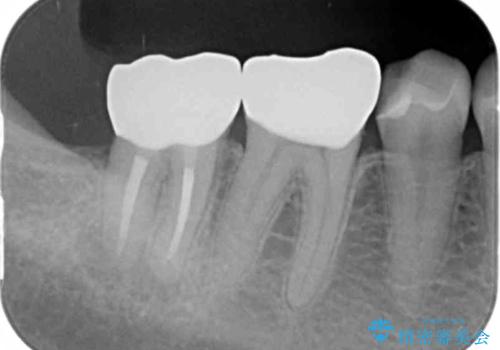

自然な仕上がりに、満足いただくことができました。

今後他の銀歯も外していく予定です。